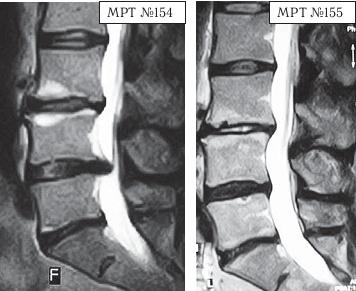

На МРТ № 158 наблюдается состояние поясничного отдела позвоночника после хирургической операции в сегменте LV—SI и образовавшаяся секвестрированная грыжа межпозвонкового диска в сегменте LIV-LV с каудальной (вниз) миграцией секвестра вдоль тела позвонка LV, сужение просвета спинномозгового канала (стеноз). На МРТ № 159 — состояние поясничного отдела позвоночника после лечения методом вертеброревитологии: отсутствие грыжи межпозвонкового диска в сегменте LIV-LV, ширина в данном участке спинномозгового канала восстановлена до естественной его нормы. Конечно, с позиции наблюдателя, неискушённого в тонкостях вариабельности различных коварных патологий, МРТ № 158, после вышерассмотренных грыж значительных размеров, мягко говоря, не впечатляет. Но специалисты, надеюсь, прекрасно понимают, насколько это сложный случай, даже по сравнению с эпизодами наличия больших секвестрированных грыж. Думаю, что подробности этого случая будет интересно узнать также и вам, уважаемый читатель. Дело в том, что у данного пациента по природе довольно суженный спинномозговой канал, то есть, говоря медицинским языком, наблюдается стеноз спинномозгового канала первого типа (врождённый). А здесь ещё и такое осложнение: длительная локализация секвестра грыжи вследствие постоянных воспалительных процессов вызвала гипертрофию задней продольной связки и своеобразно «подпаялась» к ней. Таким образом, подобная патология (секвестр) значительно усугубила ситуацию: практически на 50 % дополнительно сузила и так изначально врождённый узкий спинномозговой канал. Естественно, у пациента появились боли и слабость в обеих ногах. |